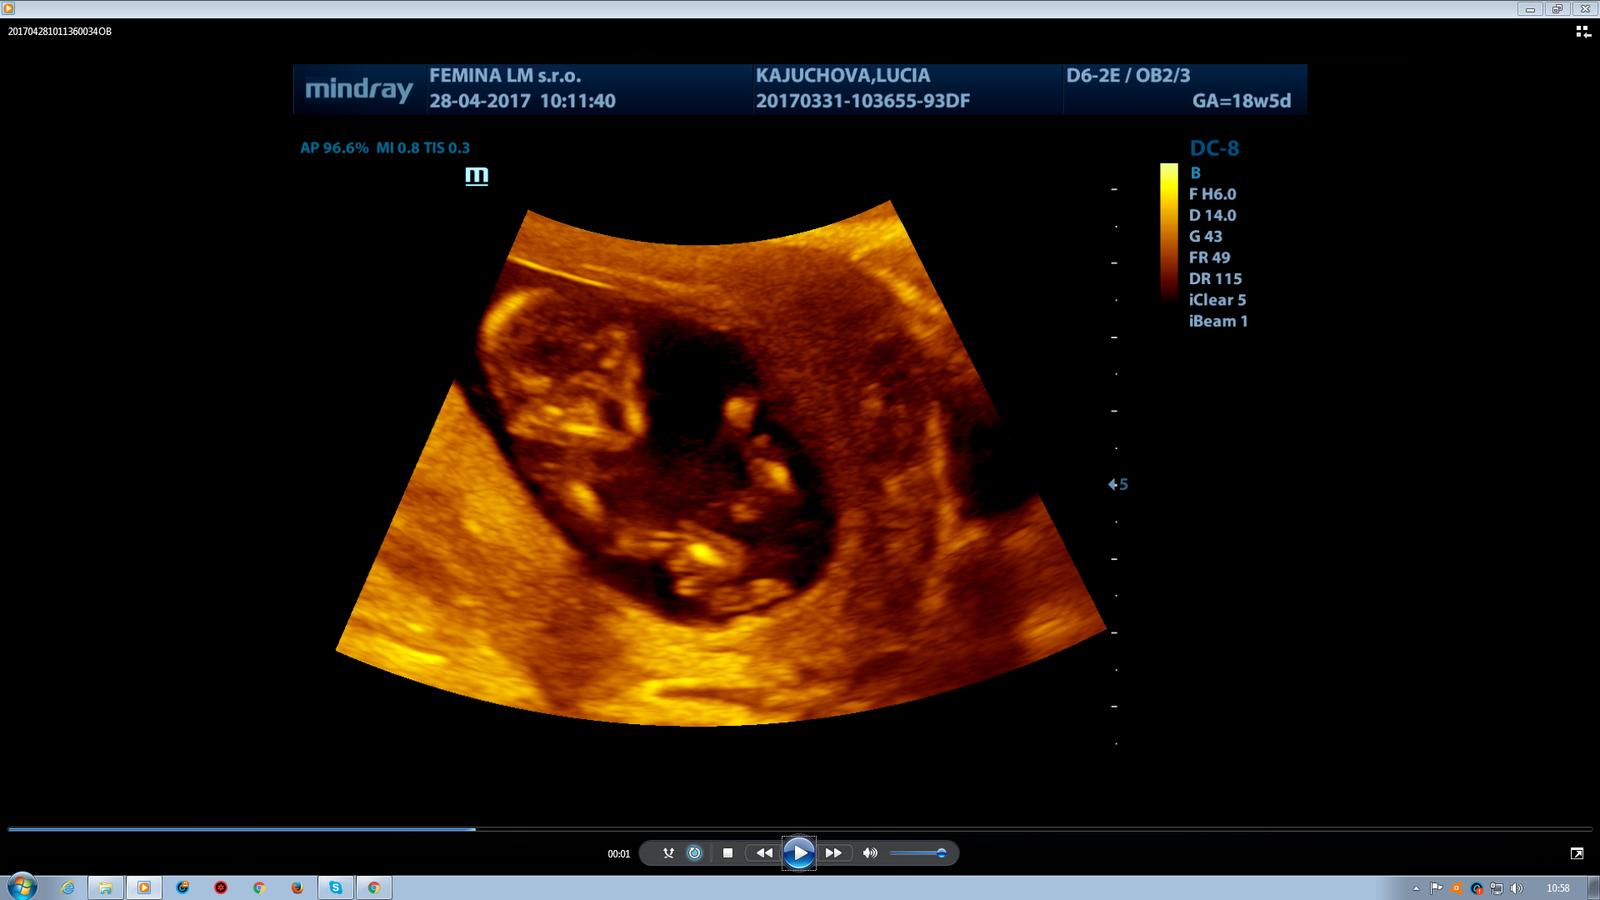

@luta13 tak baby uz mam po.vsetko v poriadku. NT nezameral lebo bolo zle otocene naša láska mala krasna :D ale povedal ze keby je to zle tak to by bolo vidno čiže sa nemam bat ze to je urcite dobre. A dalej videl medzi nožičkami tri pásiky takze pravdepodobne dievčatko ale nje je to na 100% 🙂